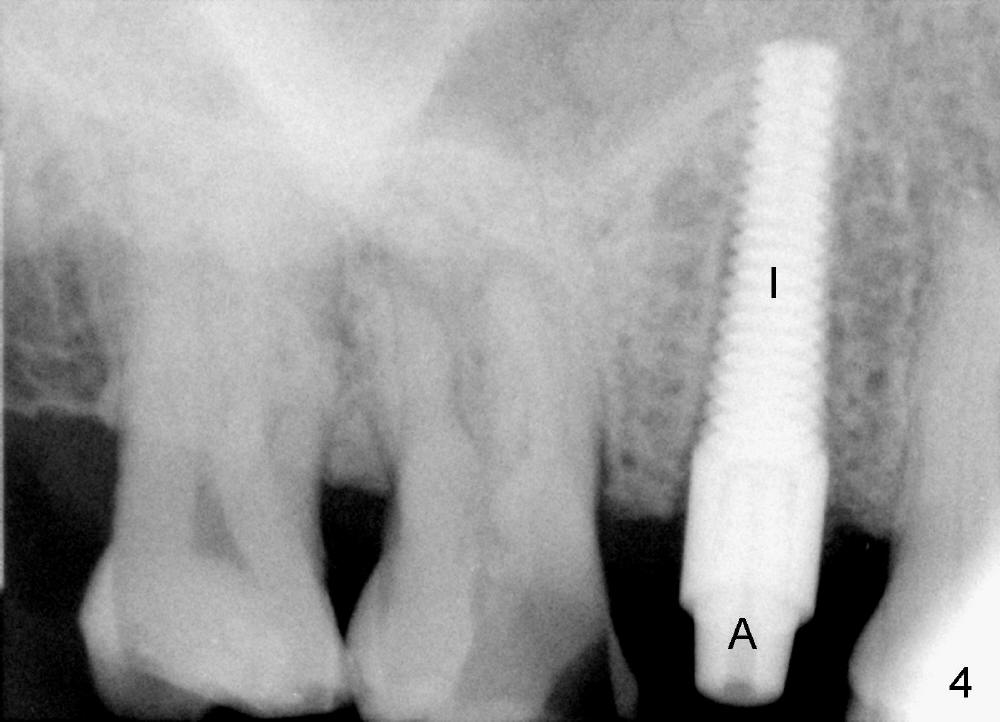

A 72-year-old man is a bruxer with #3 cusp fracture with chronic periapical radiolucency (Fig.1 *) and #4 acute crack.  It appears reasonable to take care of emergency (#4 extraction and immediate implant (Fig.3-7: 4.5x20 mm, 45 Ncm)) followed by root canal therapy or extraction for #3.  Eight (Fig.8) and 14 (Fig.9-11) days postop, the patient is doing fine and the wound heals normally.  But he does not agree any treatment for #3, since it is asymptomatic in spite of a fistula associated with the tooth (Fig.8,9 >).  Three months postop, the patient is still asymptomatic and is ready for #4 restoration since the tooth #28 cracks.  Follow-up PA shows the persistent distal gap (Fig.12 >, as compared to Fig.4), accompanied with crestal bone resorption (*).  Clinically the implant has mild mobility and light tenderness. The patient still refuses #3 treatment. It appears that the implant has failed to osteointegrate.  In brief, do not place an immediate implant next to active infection.